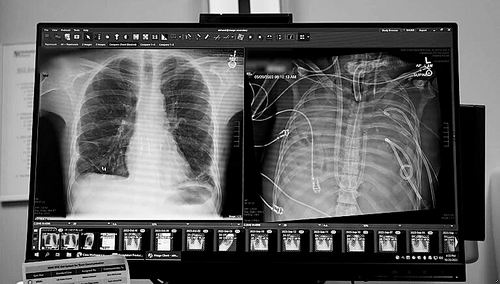

X光片显示的一名33岁患者的新肺(左)和旧肺 图片来源:美国西北大学